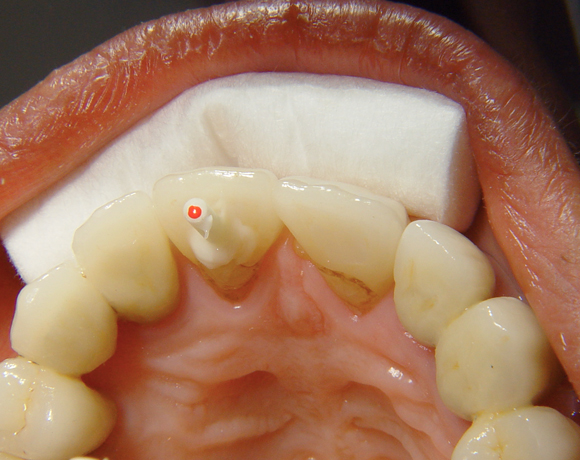

Bei diesem Patientenfall musste nach Neuüberkronung der Frontzähne eine Wurzelbehandlung erfolgen. Um der Gefahr aus dem Weg zu gehen, dass die neue Krone abbricht, da sehr wenig eigene Zahnrestsubstanz nach der endodontischen Behandlung übriggeblieben war, wurde der Zahn nachträglich mit einem Dentinpost versorgt.